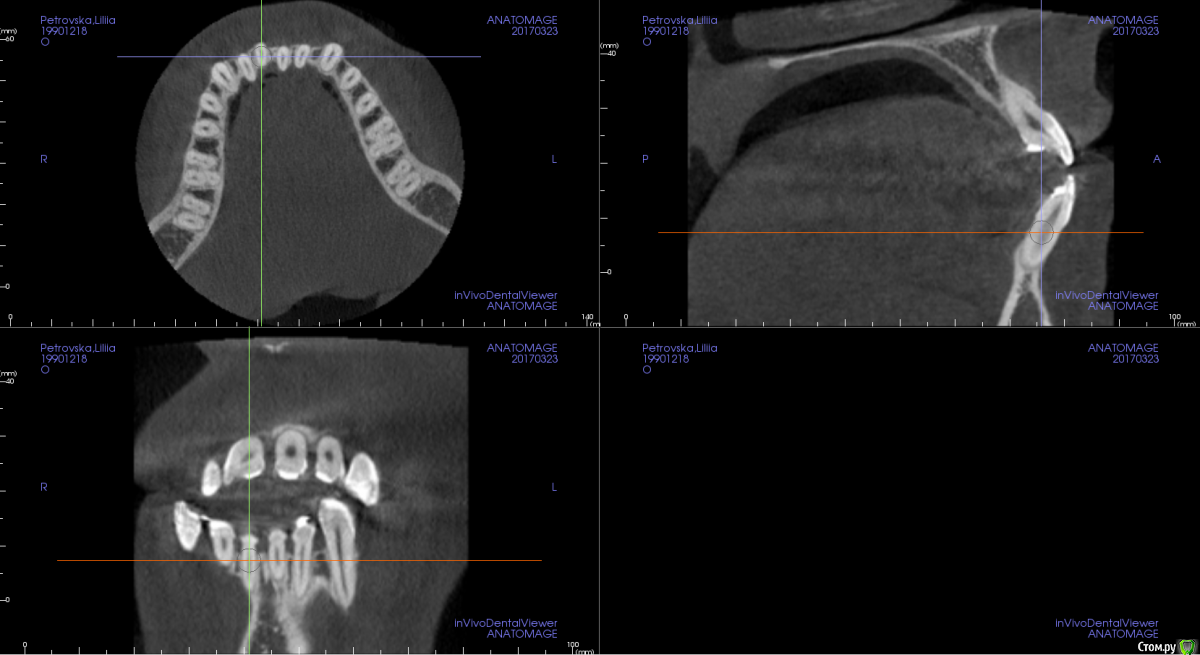

m.d.n Опубликовано 20 марта, 2017 Поделиться Опубликовано 20 марта, 2017 срезы кт покажите . на чем остановились Ссылка на комментарий

Opdihatop Опубликовано 26 марта, 2017 Автор Поделиться Опубликовано 26 марта, 2017 Прошу:313233414243 Ссылка на комментарий